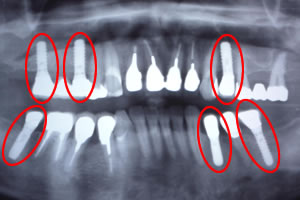

インプラント歯を抜いてしまったりして、元になる歯がない場合に、顎(あご)の骨に人工の歯根を作り、その上に歯を形成します。 歯根になる部分には「チタン」という素材を使いますが、顎(あご)の骨に良くなじむため、自分の歯と同様に使うことが出来ます。 症例1![]() 処置前